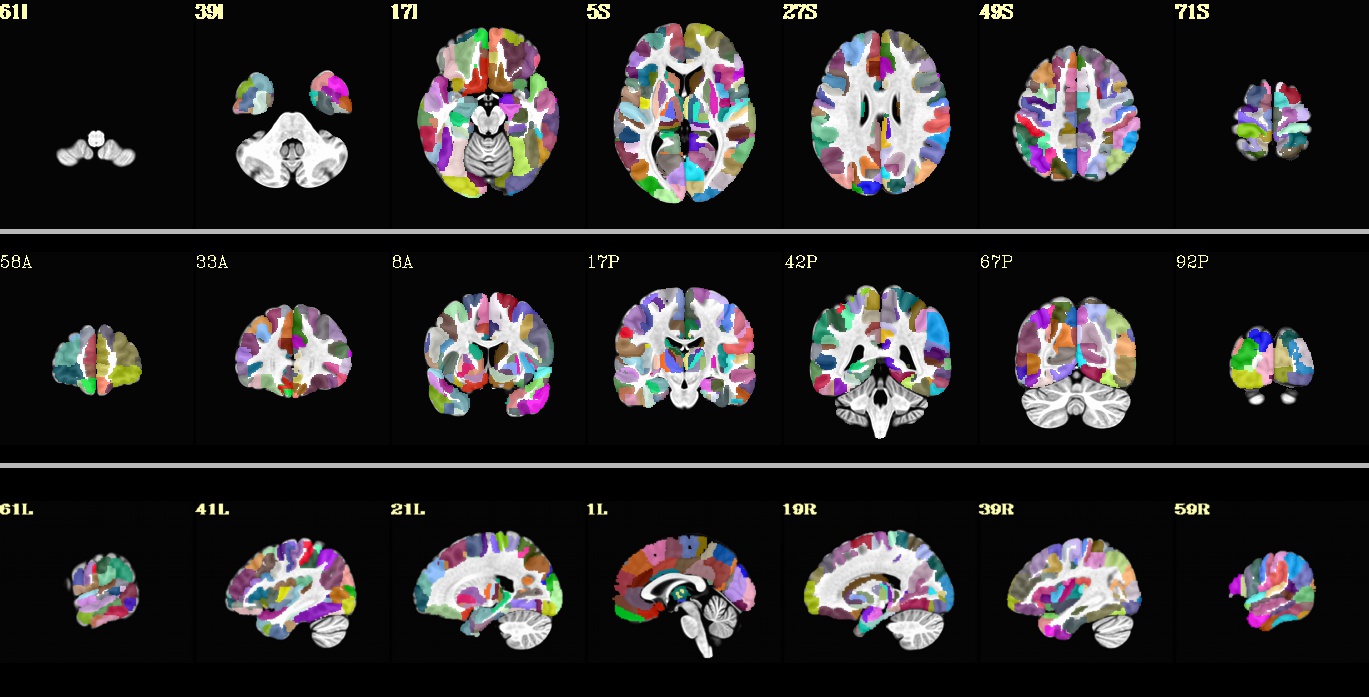

FS.afni.MNI2009c_asym.nii.gz¶

Underlay: MNI152_2009_template_SSW.nii.gz |

FS.afni.TTN27.nii.gz¶

Underlay: TT_N27_SSW.nii.gz |